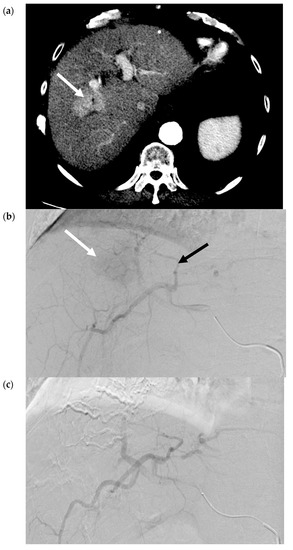

- Ogata, S.; Belghiti, J.; Farges, O.; Varma, D.; Sibert, A.; Vilgrain, V. Sequential arterial and portal vein embolizations before right hepatectomy in patients with cirrhosis and hepatocellular carcinoma. Br. J. Surg. 2006, 93, 1091–1098. [Google Scholar] [CrossRef]

- Yoo, H.; Kim, J.-H.; Ko, G.-Y.; Kim, K.W.; Gwon, N.I.; Lee, S.-G.; Hwang, S. Sequential Transcatheter Arterial Chemoembolization and Portal Vein Embolization versus Portal Vein Embolization Only before Major Hepatectomy for Patients with Hepatocellular Carcinoma. Ann. Surg. Oncol. 2010, 18, 1251–1257. [Google Scholar] [CrossRef]